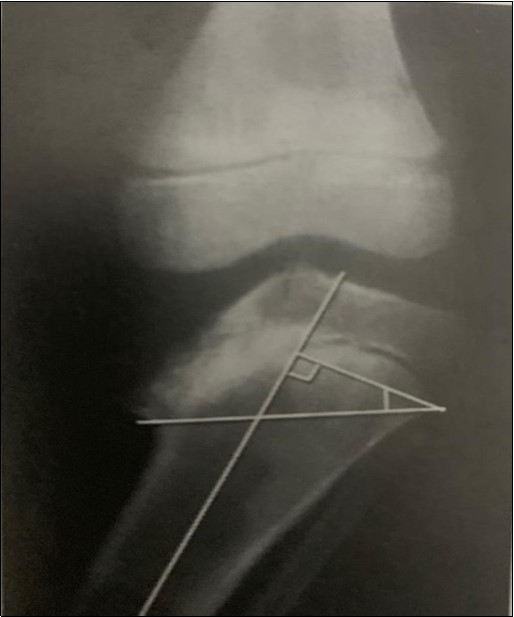

Figure2 depicts the measurement of the metaphyseo-diaphyseal angle which is another method for classifying the disease. A line is drawn perpendicular to the long axis of the tibia and another across the metaphyseal flare. The acute angle formed by these two lines should normally not exceed 11 degrees 7.

Figure 2.These classification systems are employed to aid diagnosis, monitor progression and to guide treatment of the disease 13

The metaphyseo-diaphyseal angle (MDA) better correlates with treatment outcomes as compared with the Langenskiold classification system 14.